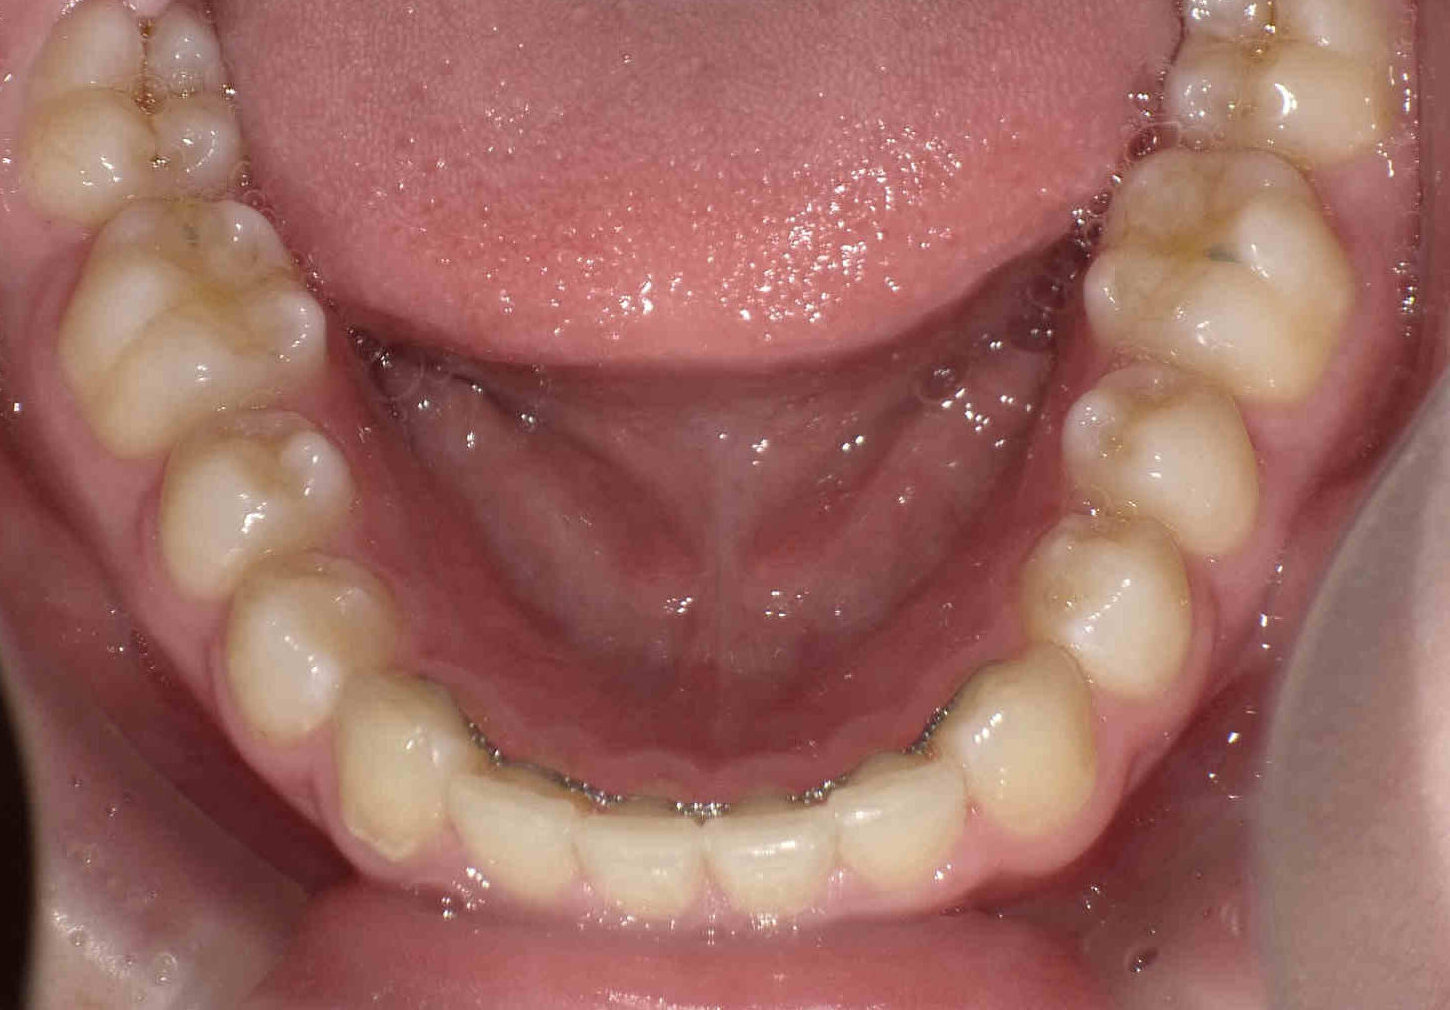

12歳6ヶ月〜スタートです。

やや出っ歯傾向で、噛み合わせが深く

歯並びがデコボコな鋏上咬合(はさみじょうこうごう)という状況でした。

上下の歯がすれ違っている状態で、一部の歯に過度の負担がかかってしまいます。

今回はご希望のワイヤー矯正で治療を行い、スタートから1年半で美しい歯並びに改善しました。